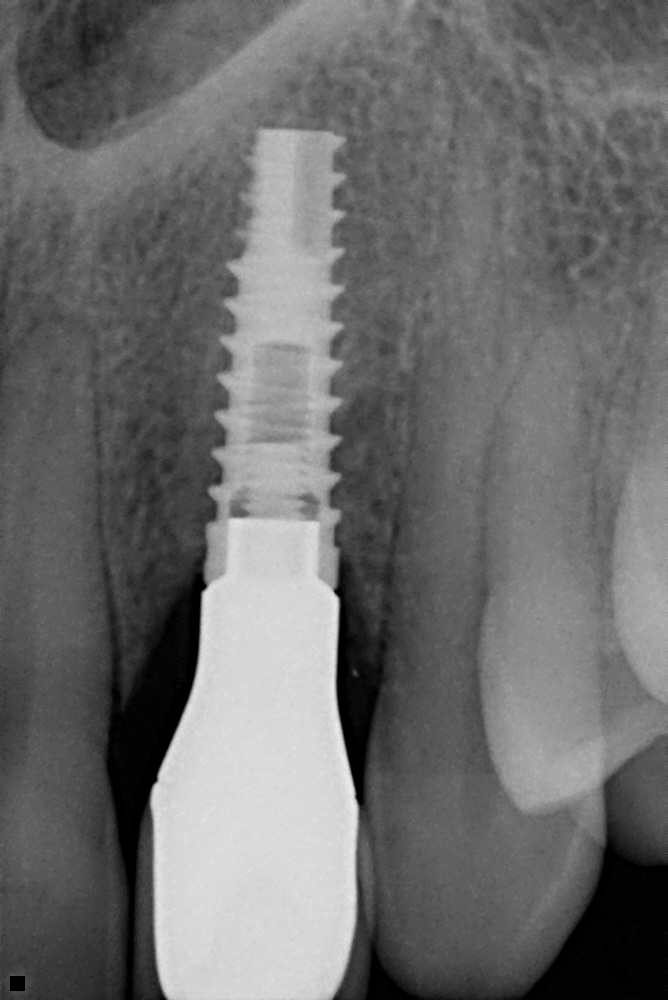

Case #4

Immediate implant.

- Fractured non-sealable tooth needed to be extracted

- Implant placed, restored with permanent crown.

- Custom zirconia crown abutment.

- Cemented all porcelain crown abutment.